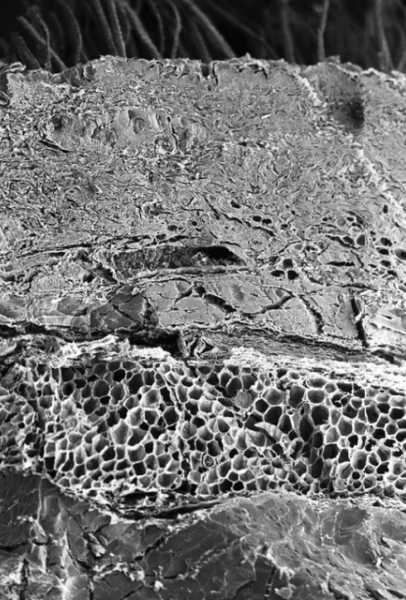

Шкіра.